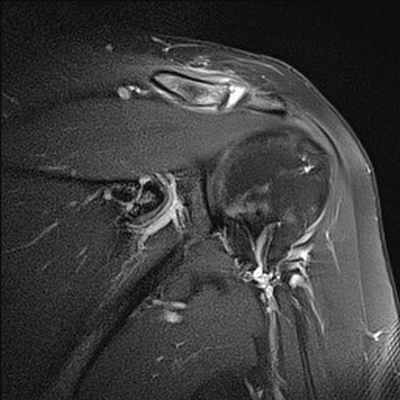

Разрывы вращательной манжеты плеча являются наиболее частой причиной болевого синдрома в плечевом суставе во всех возрастных группах взрослого населения и невозможности поднять или отвести руку. МРТ диагностика при данной травме позволяет визуализировать как полный разрыв связок, так и частичное их повреждение. Как правило, сопутствующими осложнениями повреждений вращательной манжеты плеча является скопление жидкости в субакромиальной и поддельтовидной сумках (находятся между мышцами), что также хорошо выявляется при МРТ исследовании. А восстановление разрыва сухожилий вращательной манжеты является сложной хирургической операцией.

МРТ признаки повреждения акромиально-ключичного сочленения на уровне плечевого сустава

МРТ плечевого сустава